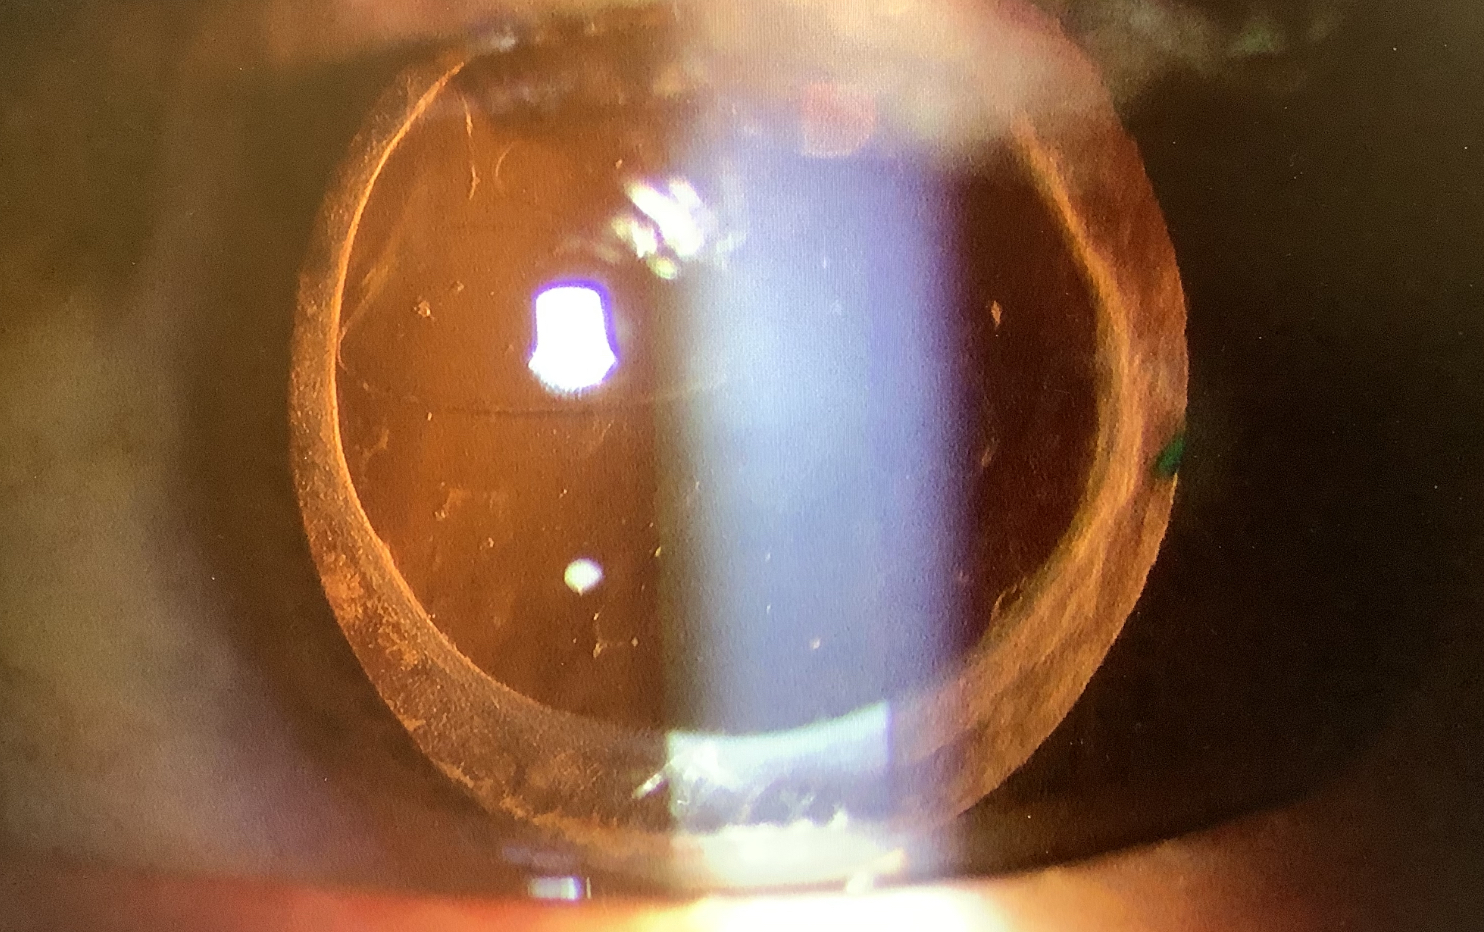

しかし、この患者さんでは、眼内レンズの裏側の水晶体嚢に穴があいているため、うまく水晶体嚢の中に新しい眼内レンズを入れられず、嚢外固定にしなければならない可能性もある程度出てしまい、その場合は、トーリックレンズが使えなくなってしまうことも考えねばなりませんでした。ある程度の遠方にピントの合わせることと乱視を減らすという2つの目的がある訳ですが、嚢外固定では乱視が残ってしまい、目的が半分しか果たせなくなってしまうことも覚悟しなければならないかと思いました。